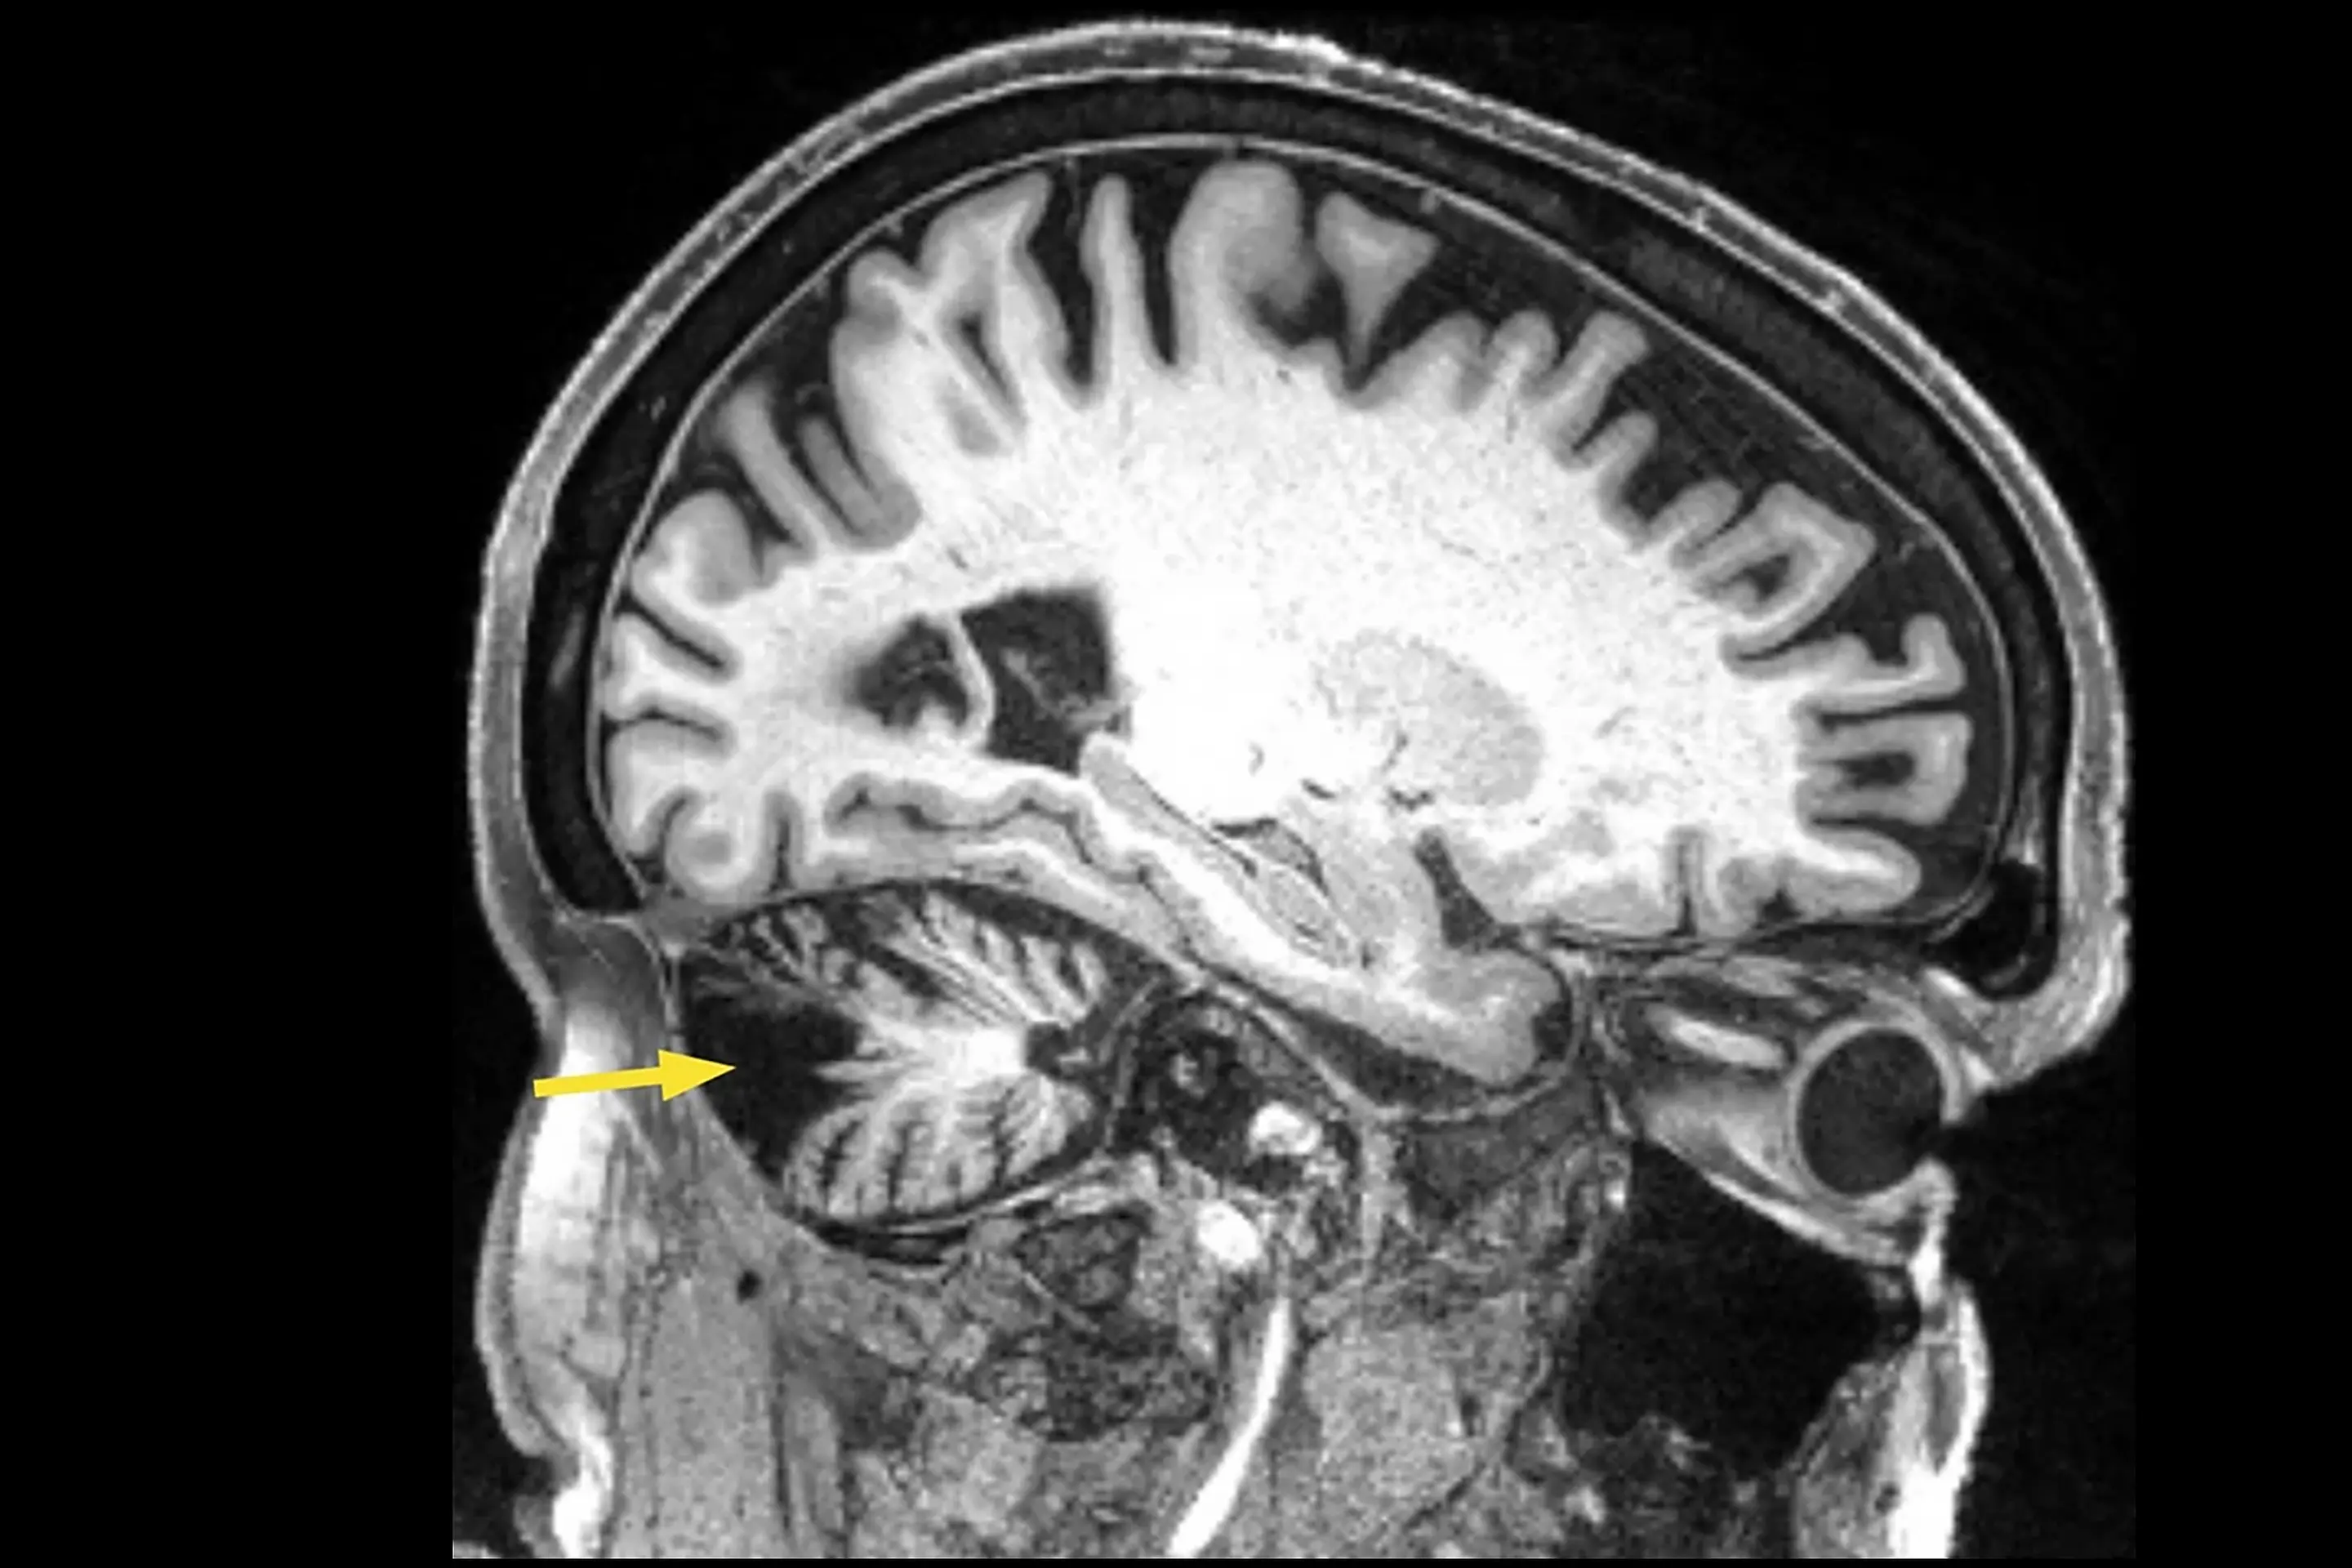

研究人员对一名 12 年前曾患小脑中风的男子的大脑进行了重复磁刺激,改善了他的行走速度、平衡和协调能力。这种创新疗法可以帮助那些在中风多年后仍然行动不便的人。中风损害了大脑的小脑(控制运动的区域),会导致共济失调,影响协调和平衡。小脑共济失调的程度从轻微到严重不等,通常表现为步态不稳、步履蹒跚、精细肌肉运动丧失、言语不清和吞咽困难。

小脑共济失调的治疗仅限于物理和职业治疗,必要时还需要进行语言治疗。不过,加州大学洛杉矶分校医疗中心的研究人员最近进行的一项病例研究描述了一种很有前景的新疗法:重复经颅磁刺激(rTMS)。

在目前的研究中,患者是一名 58 岁的男性,12 年前曾突发小脑中风,尽管进行了强化康复治疗,但步态仍然缓慢不稳,平衡和稳定性也有困难。在没有帮助的情况下,他无法从坐位站起来,也无法弯腰从地上捡起一件物品。他使用滚动助行器来保持稳定,在接受经颅磁刺激治疗前,他能以每秒 0.57 米的速度行走 10 米(32.8 英尺)。